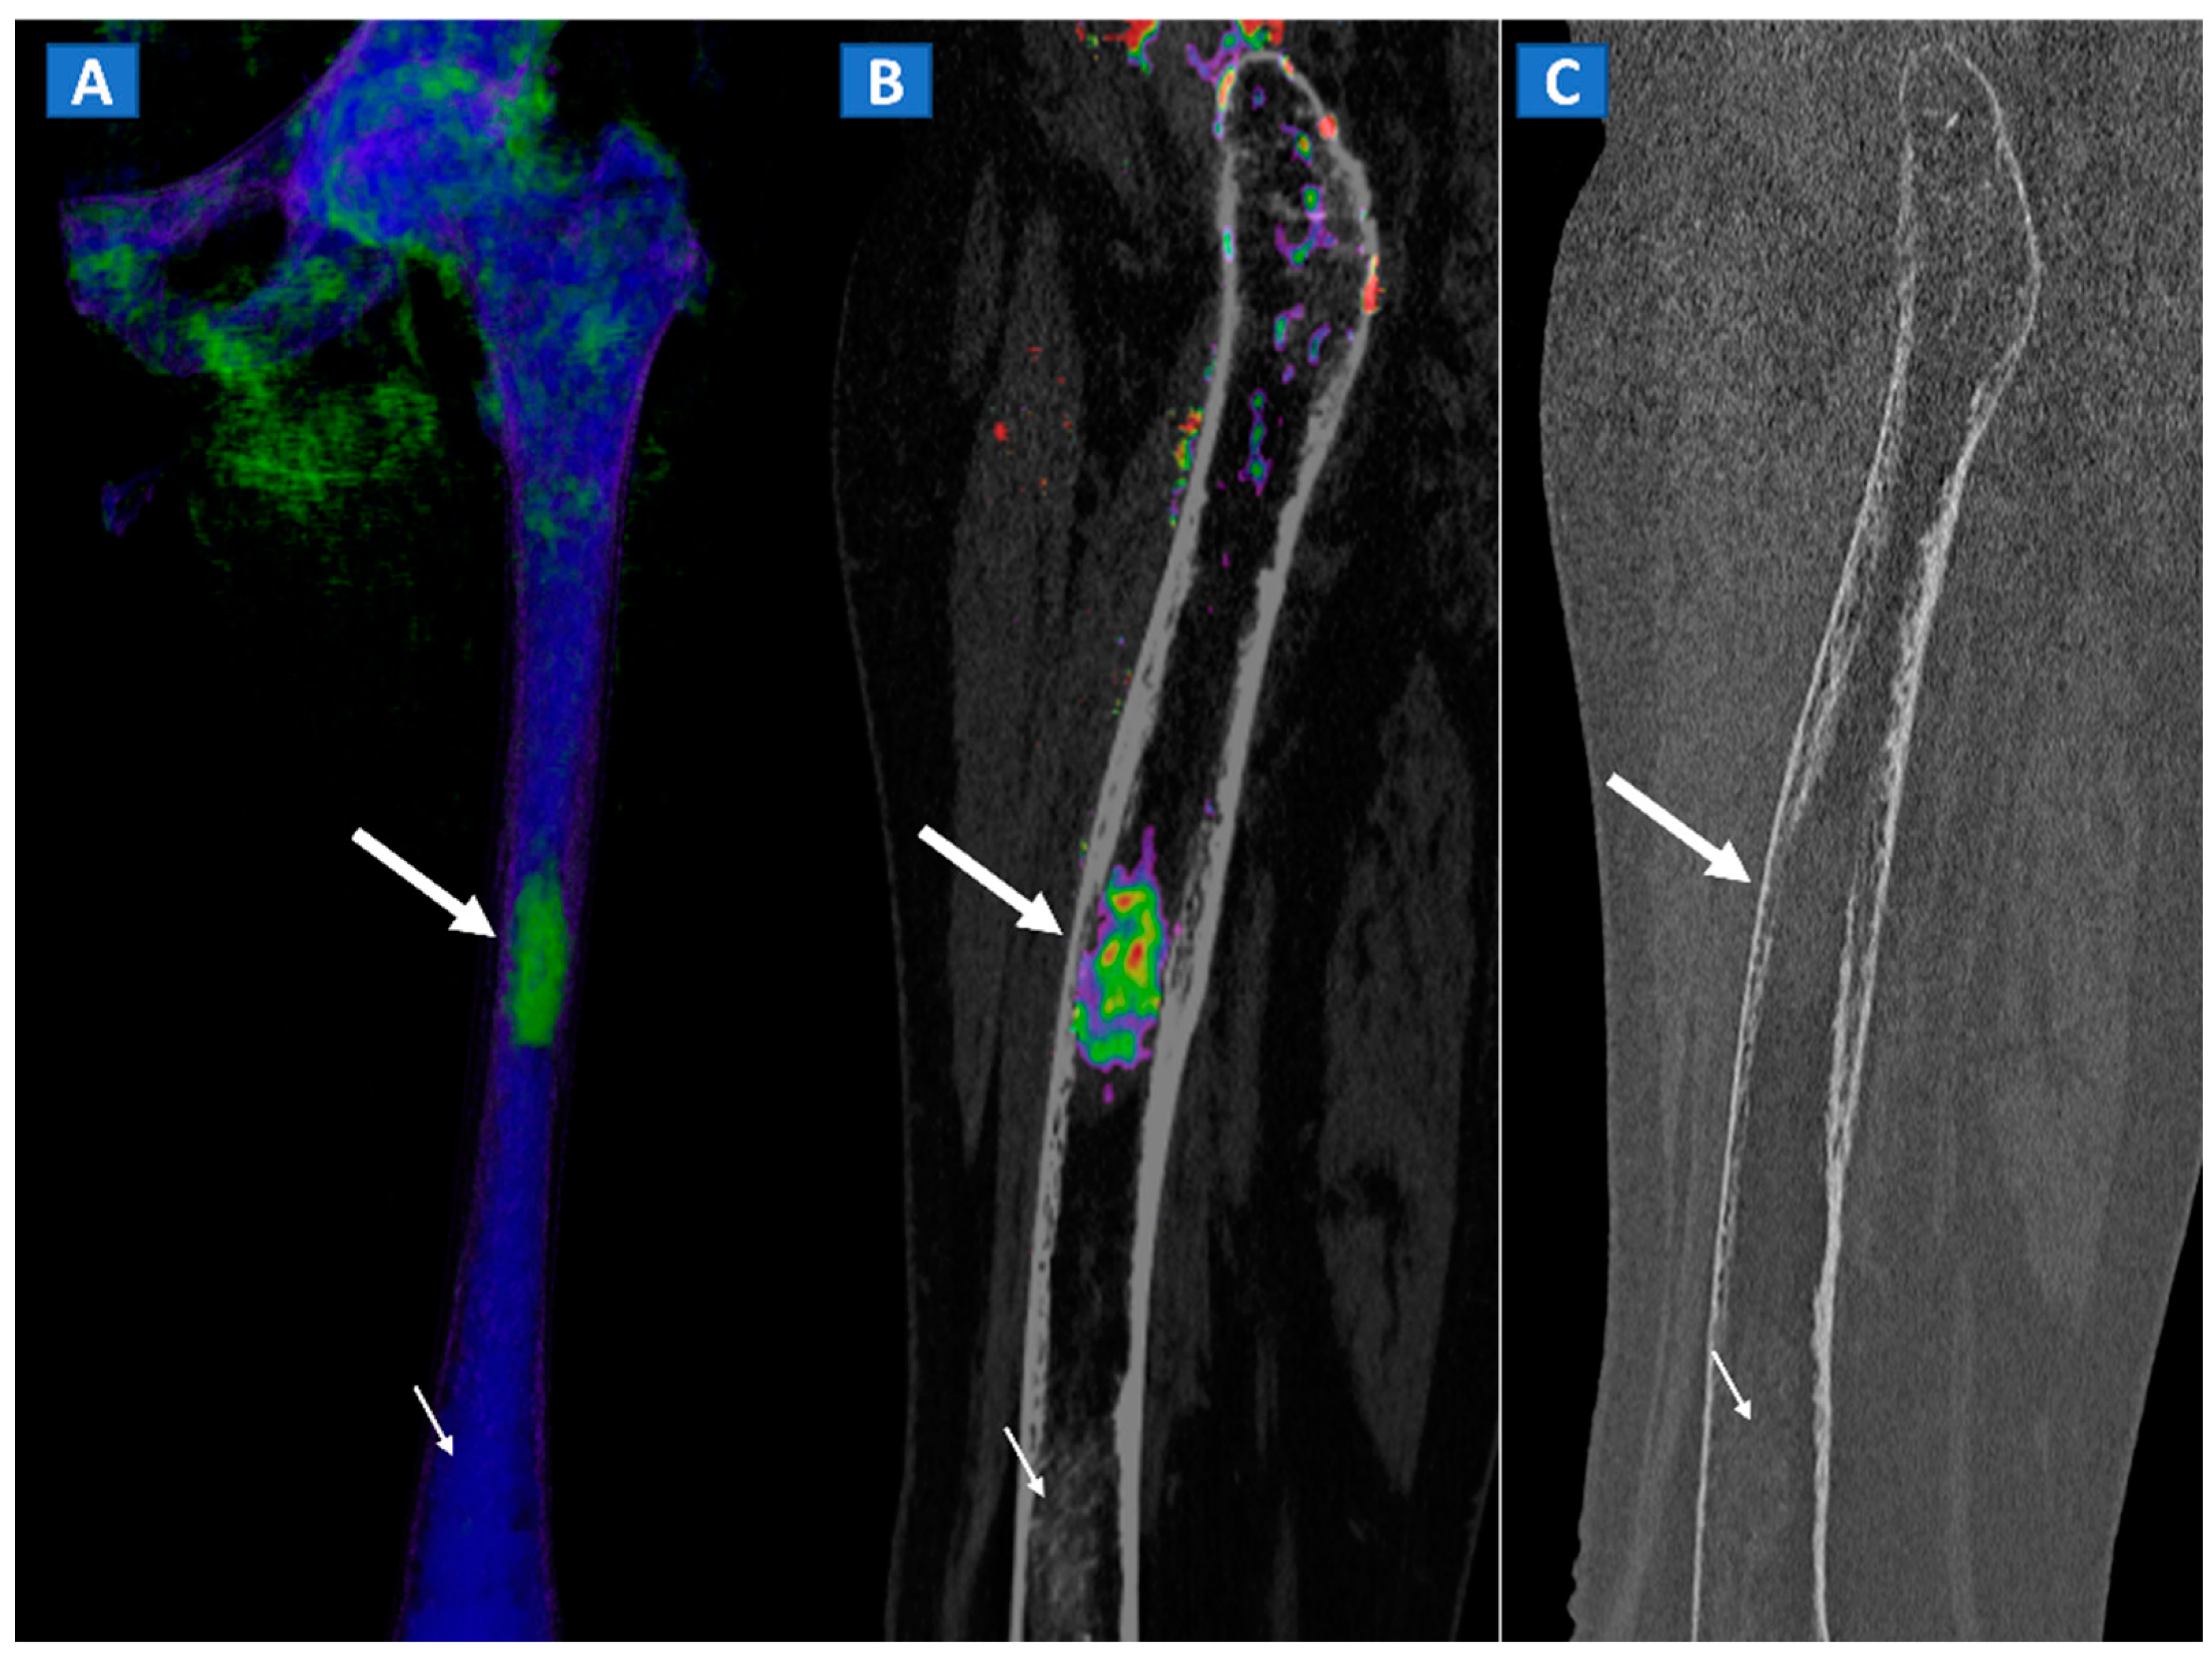

8. Transient Bone Marrow Oedema Syndrome

9. Stress or Insufficiency Fractures